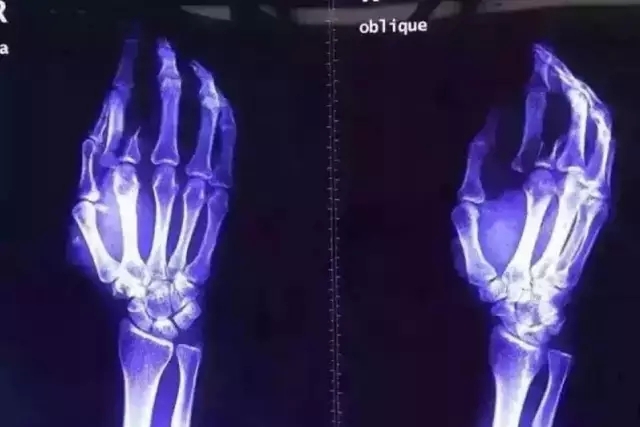

又一起傷醫(yī)事件刺痛了我的眼球,看著觸目驚心的血腥圖片,一股寒涼之氣瞬間侵入心靈,攪動(dòng)著悲憤的心情。